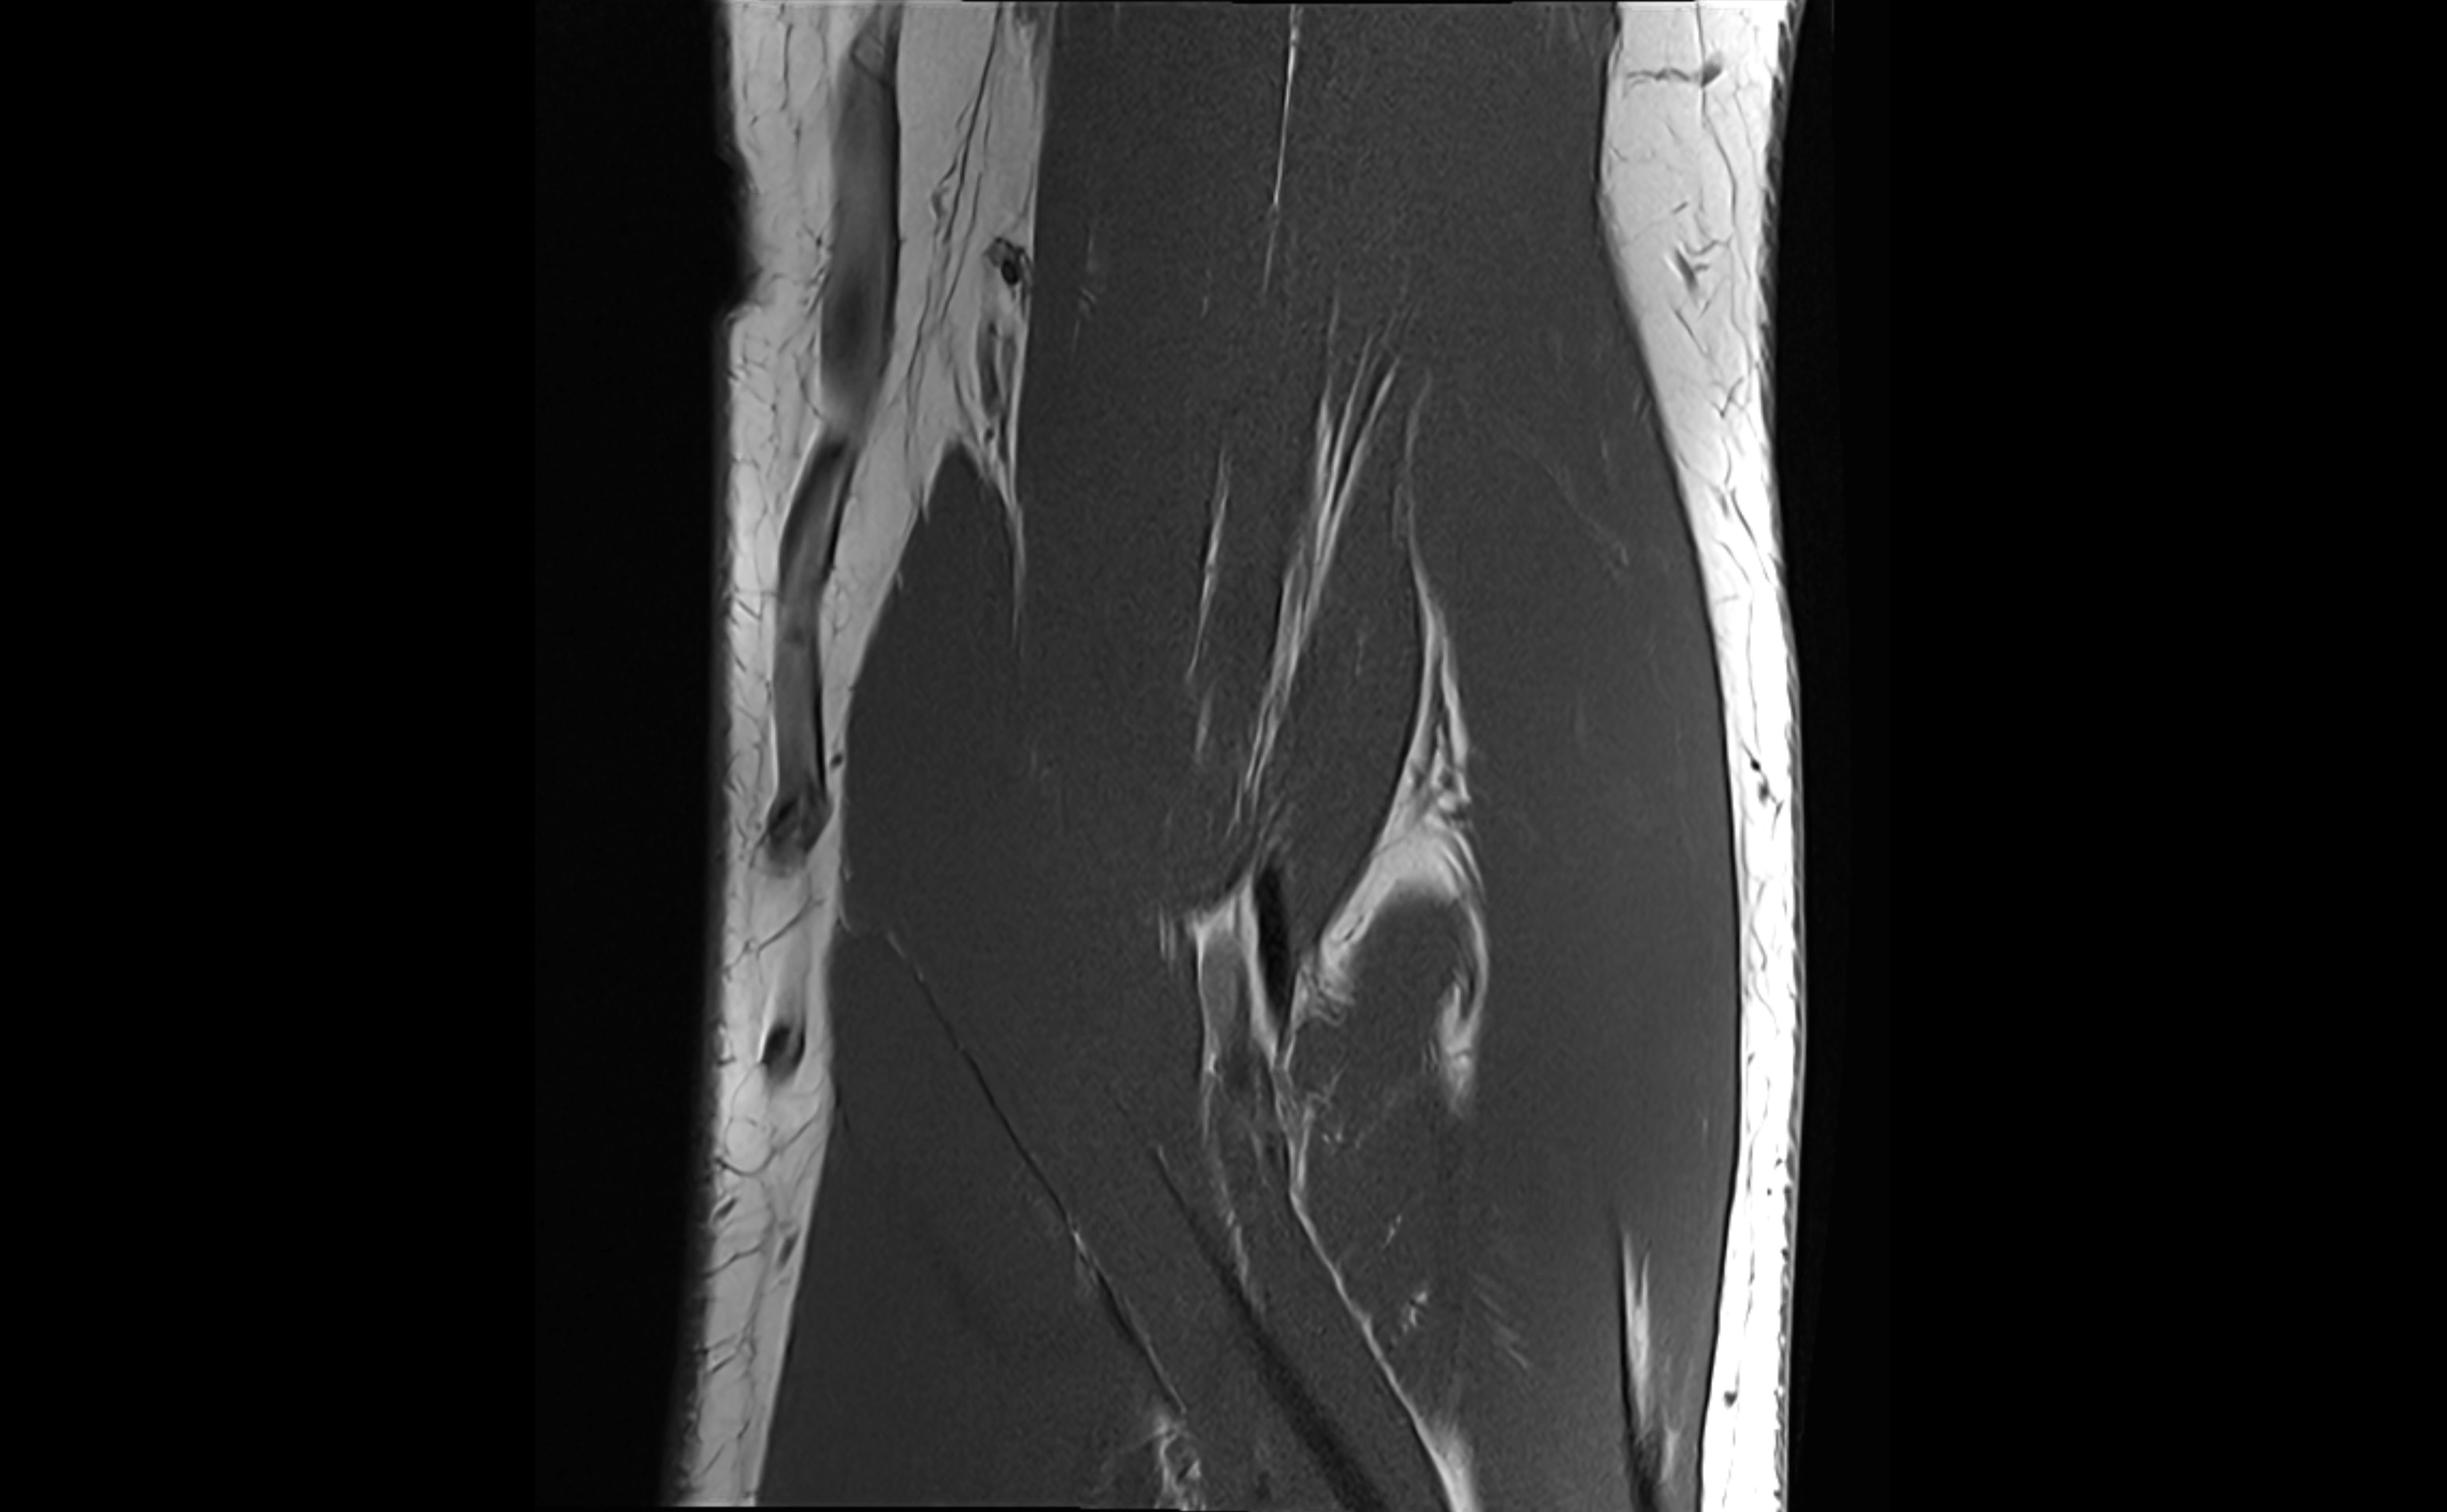

MRI images

image